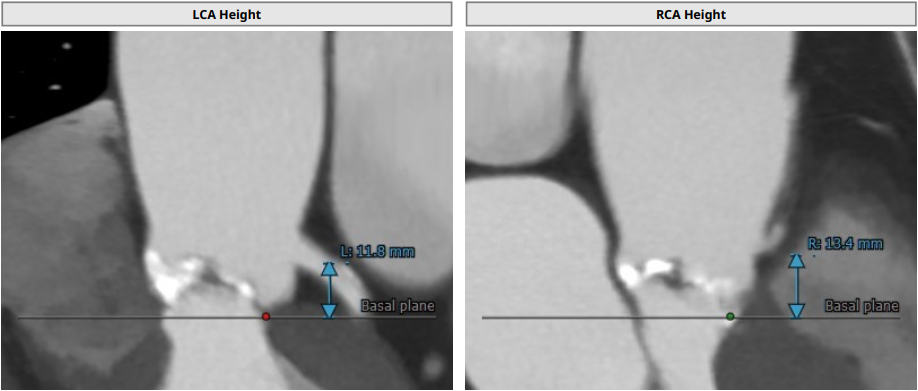

左冠开口高度:11.8 mm,右冠开口高度:13.4 mm